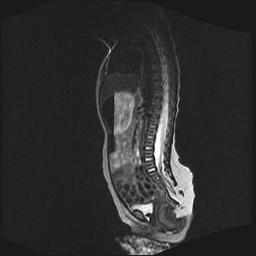

标题: PED0016:脊膜膨出 [打印本页]

标题: PED0016:脊膜膨出

四个月的女婴,ct示脊膜膨出.

脊柱裂、脊膜膨出,请结合临床除外皮毛窦。

脂肪脊髓脊膜膨出

脊柱裂、脊膜膨出